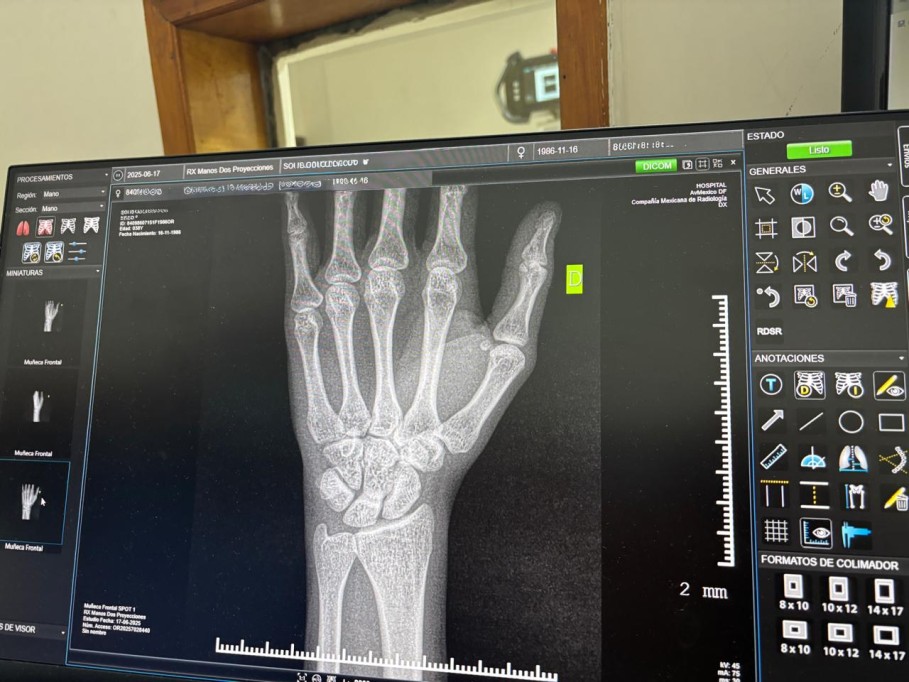

Estas condiciones debilitan la estructura esquelética y elevan el riesgo de fracturas, presentándose frecuentemente de forma asintomática en sus etapas iniciales.

El especialista señaló que es necesario solicitar valoración médica profesional ante síntomas como dolor persistente sin causa aparente, fracturas recurrentes o una disminución progresiva de la estatura.

Actualmente, el IMSS en Yucatán ofrece servicios de detección oportuna a través de los módulos PrevenIMSS, ubicados en las Unidades de Medicina Familiar. En los casos donde se detectan riesgos mayores o patologías establecidas, los pacientes son canalizados a Segundo Nivel para recibir atención especializada y seguimiento clínico.